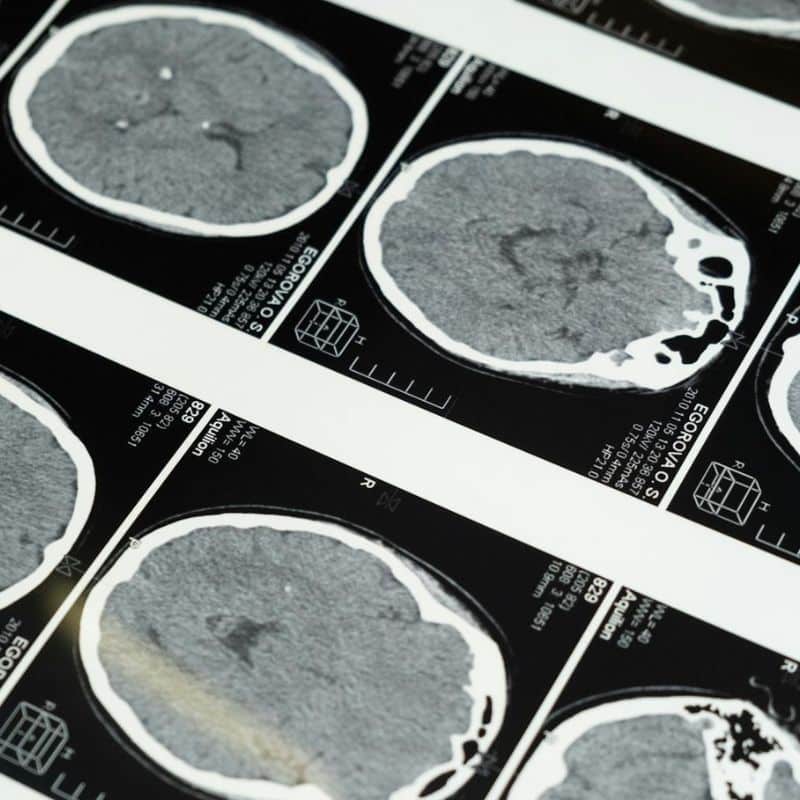

Según el portal profesional Alzheimers.gov, la enfermedad de Alzheimer se puede definir como un trastorno cerebral que destruye lentamente la memoria y la capacidad de pensar. Es la forma más común de demencia, un término que se emplea para designar a aquellas entidades clínicas que cursan con pérdida de función cerebral. Más allá del Alzheimer, en este grupo también se encuentran la demencia vascular, la enfermedad de Huntington, las lesiones cerebrales, la esclerosis múltiple, la parálisis supranuclear progresiva y muchas más.

A nivel fisiopatológico, la enfermedad de Alzheimer se caracteriza por una acumulación de placas neuríticas anormales y ovillos neurofibrilares en el cerebro. Las placas son lesiones microscópicas esféricas que se forman en los espacios interneuronales de la sustancia gris cerebral por el depósito de una proteína conocida como beta-amiloide. Los ovillos neurofibirlares son otro tipo de estructuras anormales compuestas por agrupaciones densas de filamentos helicoidales apareados que se sitúan en varias partes del cerebro. Todo esto se traduce en un proceso neurodegenerativo, lento pero constante.